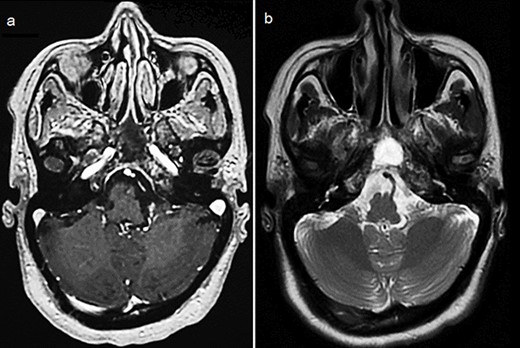

By the end of biological exploration, the patient reported a recurrence of headaches and blurred vision, 2 months after surgical decompression. Cerebral MRI revealed a relapse of the sphenoid plasmacytoma, measuring 70 mm (Fig. 3). Given the pathological diagnostic result, surgical re-intervention was not decided. Instead, the patient was treated with external beam radiotherapy (RTX) focused on the sphenoid bone (30 Gy), followed by immunochemotherapy with zoledronic acid. After 6 months, complete response was noted with the resolution of symptoms, disappearance of the monoclonal band, normalization of sFLC, and persistence of lytic sequelae on cerebral MRI (Fig. 4). Autologous stem cell transplantation (ASCT) was successfully performed, and the patient was put under treatment maintenance. After 18 months of follow-up, clinical, biological, and radiological evaluation confirmed sustained complete remission.

Control cerebral MRI (axial views) showing the disappearance of the sphenoid BP after treatment with RTX and immunochemotherapy. (a: T1-weighted; b: T2-weighted).